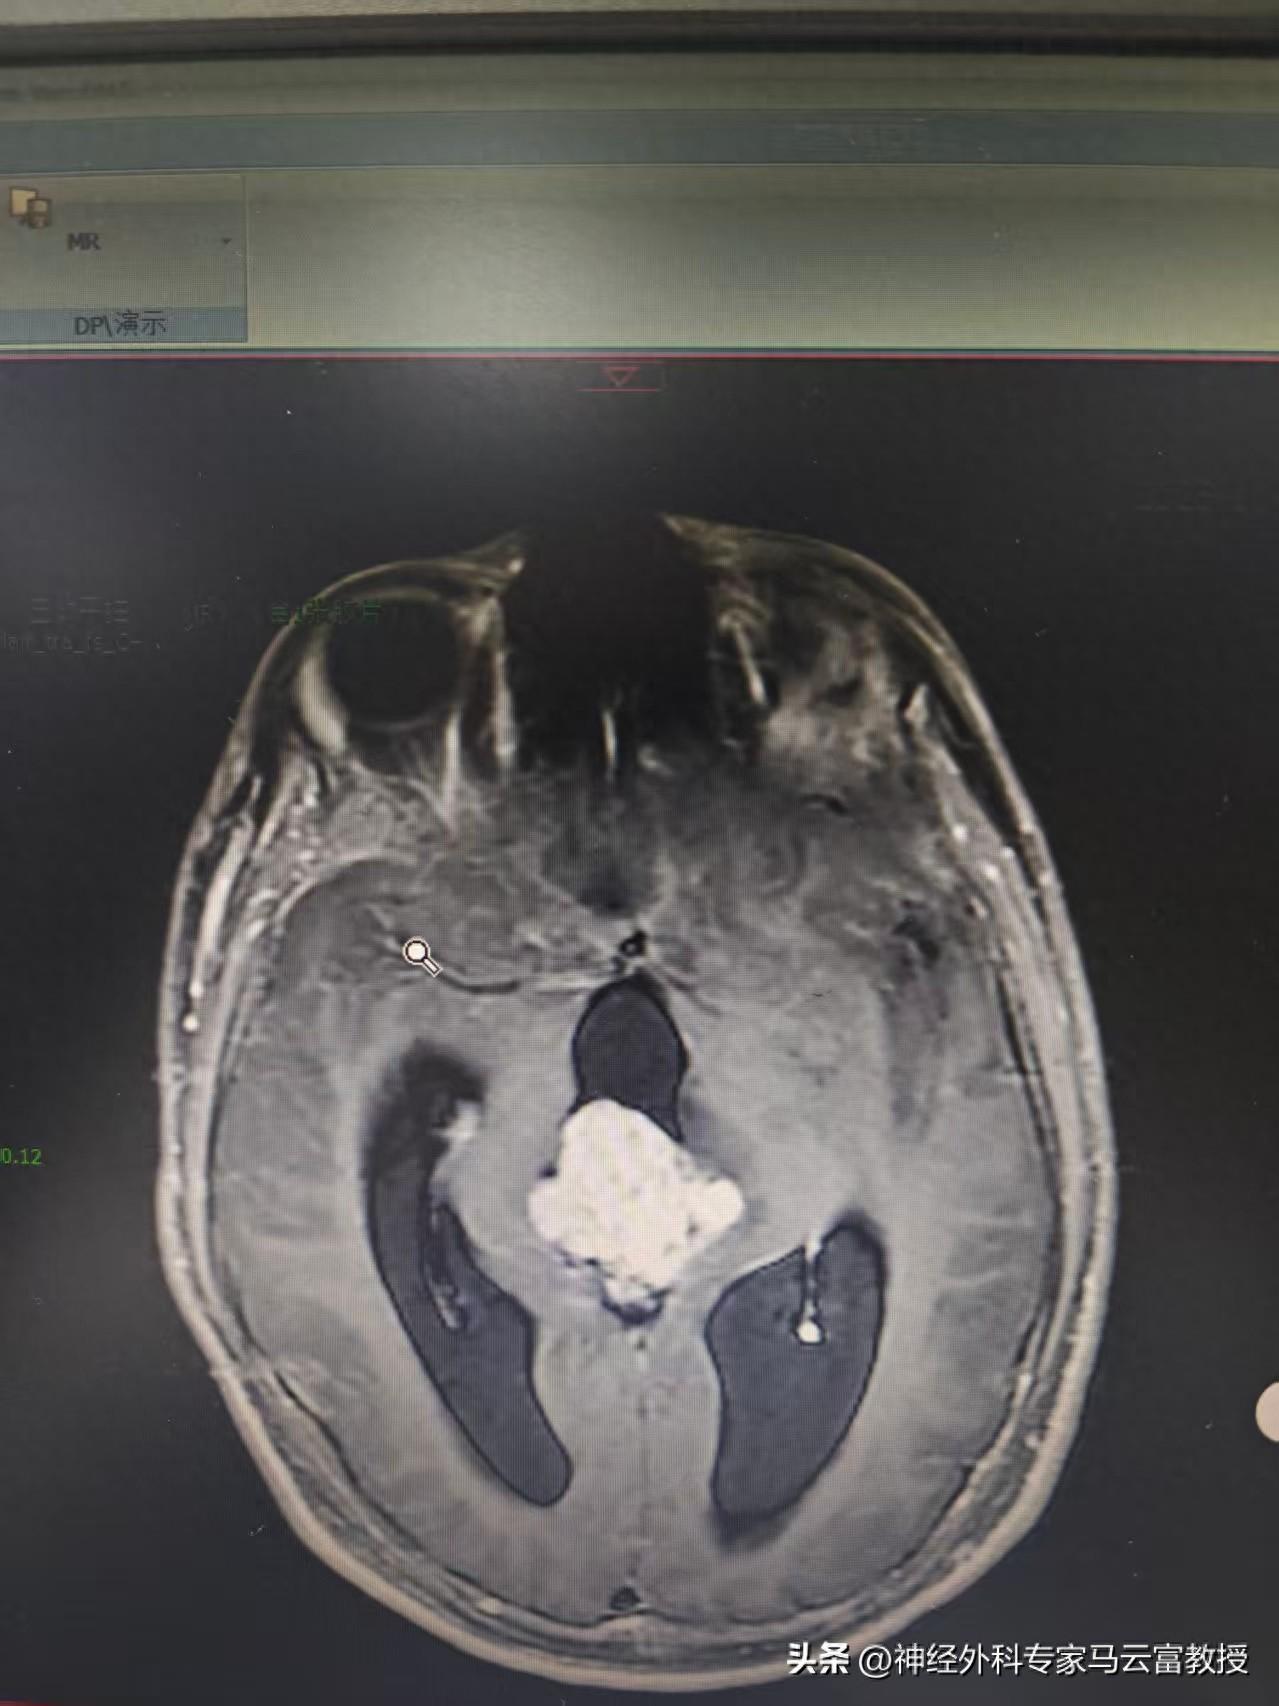

患兒小明(化名)原本活潑健康,近期卻逐漸出現雙眼視力減退,偶有頭暈,並伴有噁心嘔吐。父母察覺異常後,帶其至我院光谷院區就診。經頭顱MR檢查提示:松果體區存在混合信號佔位(考慮生殖細胞腫瘤可能),鄰近背側丘腦受壓水腫,幕上腦室已出現梗阻性腦積水。

腦MRI

腦MRI圖片